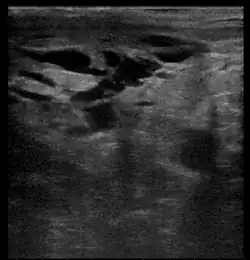

Breast ultrasound is the use of medical ultrasonography to perform imaging of the breast. It can be used as either a diagnostic or a screening procedure.[38] It may be used either with or without a mammogram.[39]

Diagnostic anatomic ultrasound looks at the anatomy whereas diagnostic functional ultrasound records information such as blood flow or tissue characteristics. A specific functional form of ultrasound is elastography which measures and displays the relative elasticity of tissues, which can be used to differentiate tumors from healthy tissue.[40] Recent studies have shown that shear wave elastography in primary invasive breast carcinoma could be useful for indicating axillary lymphadenopathy.[41]

Ultrasound is also used surgically. Specifically, an ultrasound-guided needle biopsy allows providers to see the needle so it can be directed toward the lesion of concern while avoiding other critical structures such as blood vessels.[40] Ultrasound-guided biopsies have also been shown to decrease re-excision and mastectomy rates in breast cancer. A recent study found 100% ultrasound localization with negative margins obtained in both non-palpable and palpable lesions at initial procedure. In line with this, intraoperative ultrasound guided breast conserving surgery is being increasingly used by breast surgeons worldwide[42]